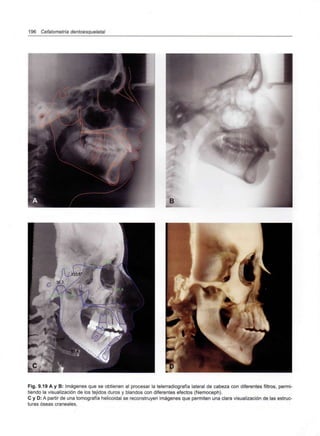

Capítulo 9 - Telerradiografía 177

Introducción 179

Tipos de telerradiografías 180

Posicionamiento de la cabeza 183

Obtención de la telerradiografía en PNC 185

Aplicación de la Horizontal Verdadera o

el plano de Frankfort para el estudio

cefalométrico 190